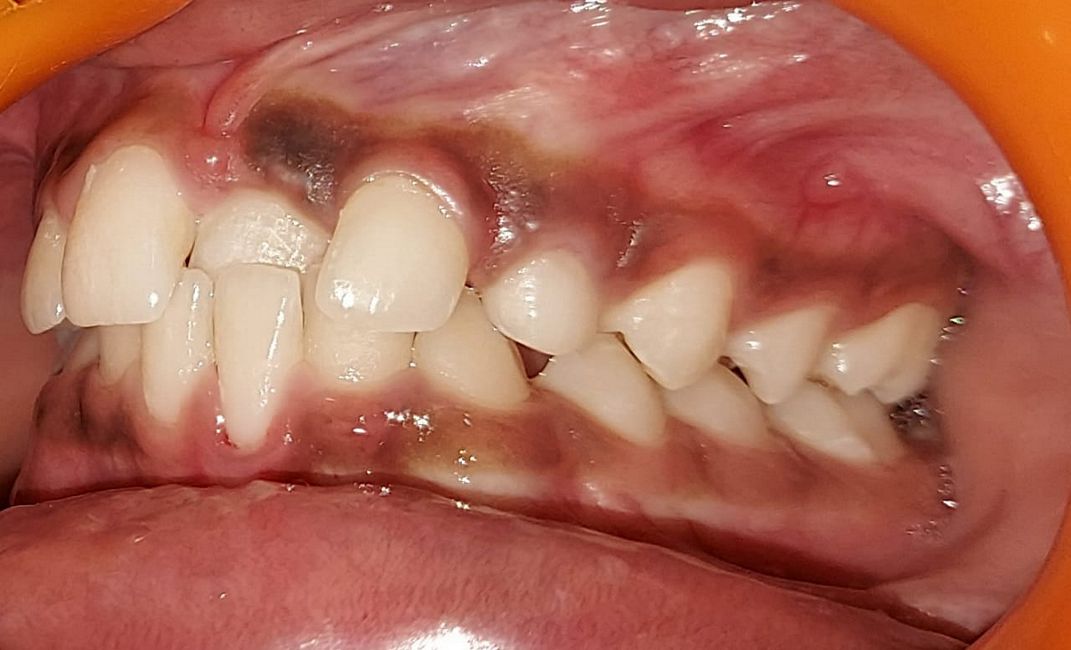

Intra-oral : Pre-treatment : Right Lateral View

Intra-oral : Post-treatment : Right Lateral View

Intra-oral : Pre, Mid & Post-treatment : Right Lateral View